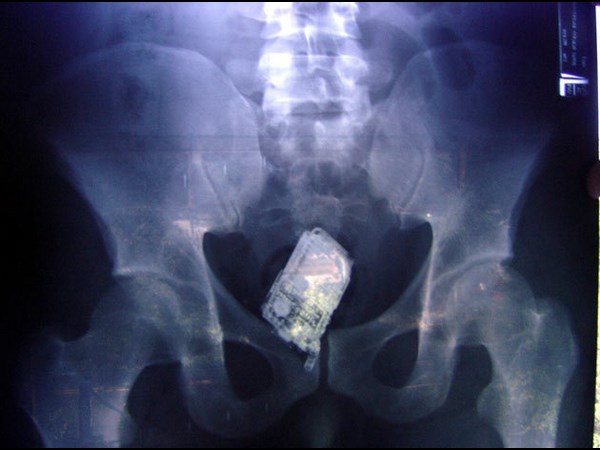

மருத்துவ உலகம் கண்டு வியந்த எக்ஸ் ரே படங்கள்

வயிற்றில் மொபைல் உள்ளது.

வயிற்றில் மொபைல்.